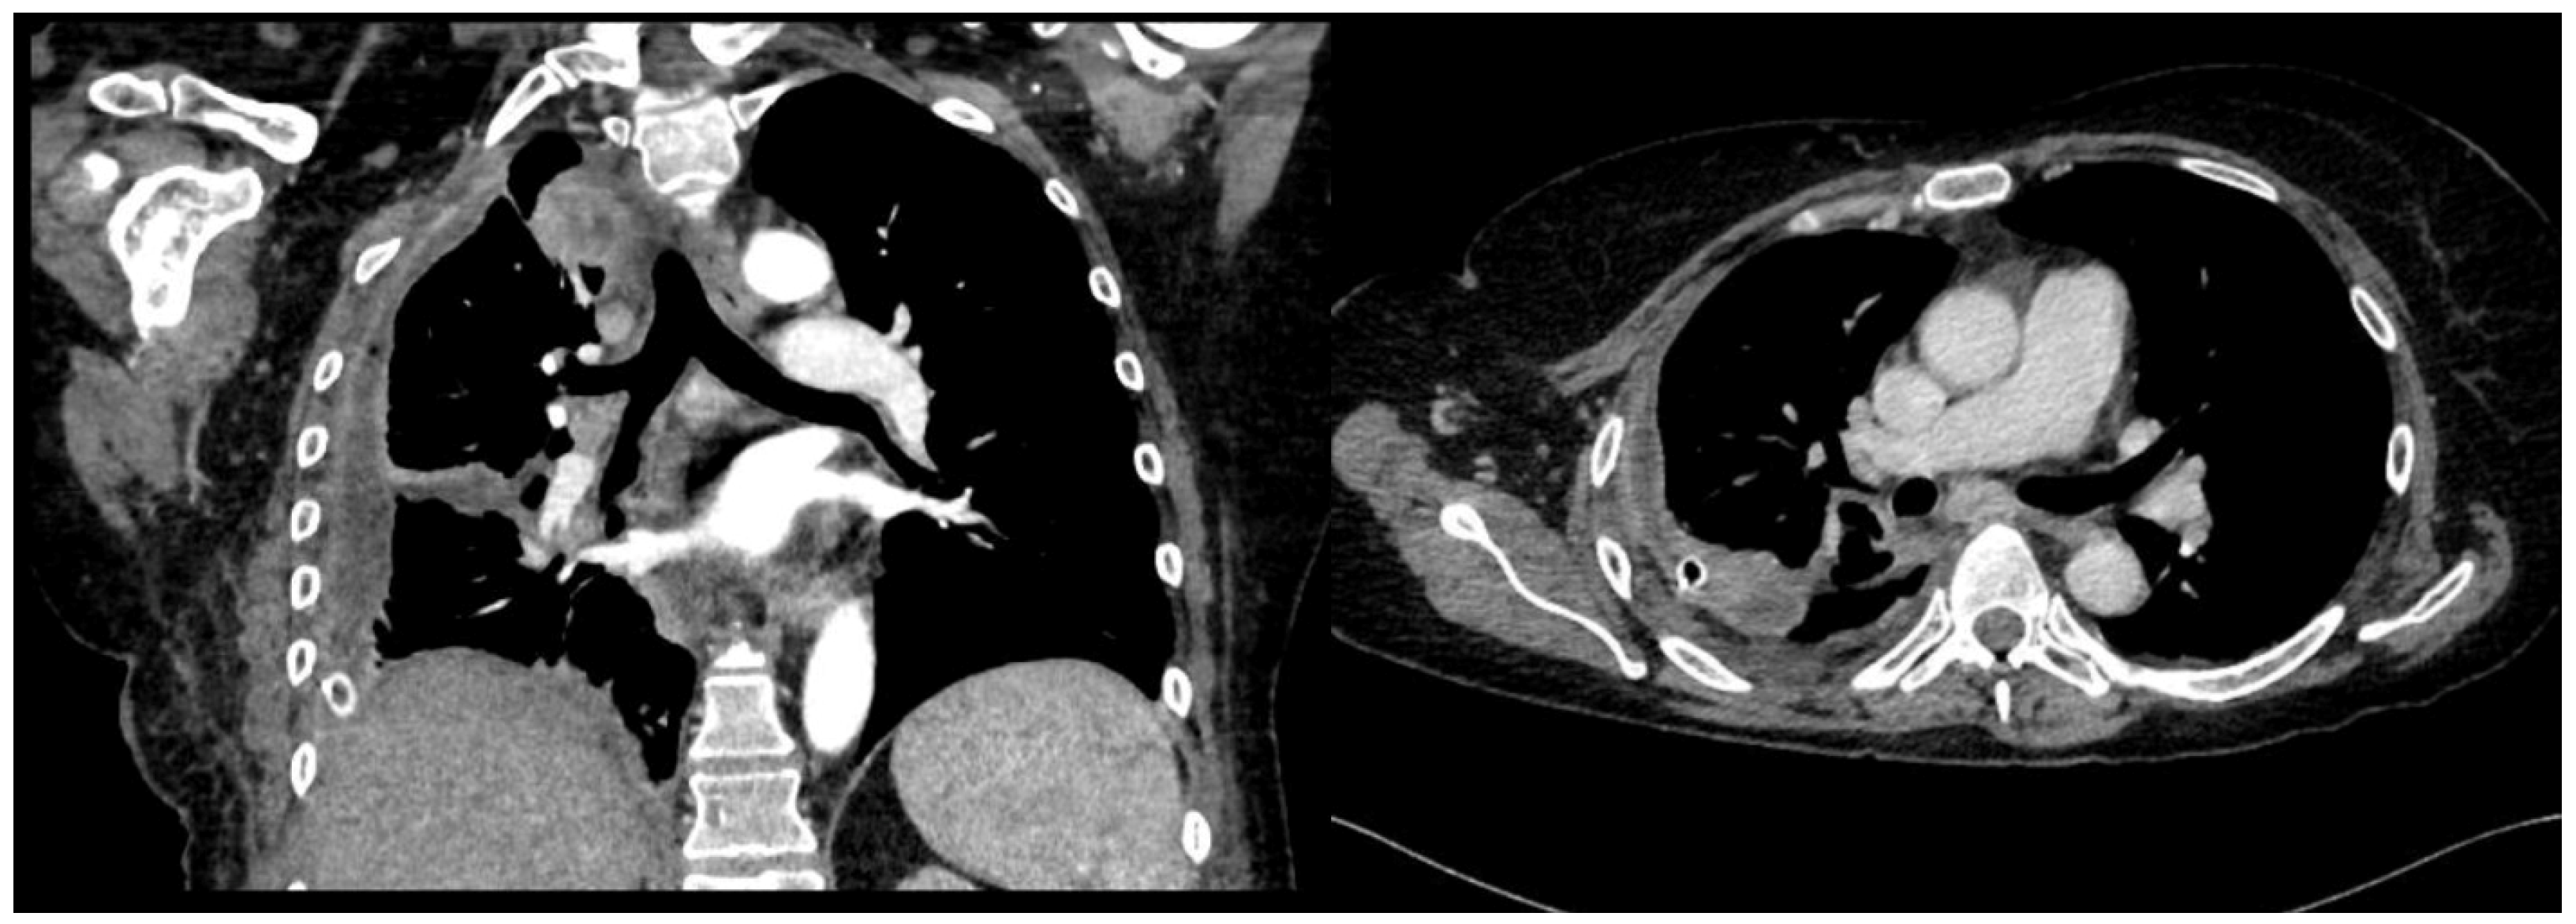

After a chest CT scan, which showed a massive effusion, the patient underwent a thoracoscopic lavage of the left pleural cavity without any complications. At the end of the surgery, two left thoracic drains were left in place, through which repeated irrigation of the pleural cavity with urokinase was performed under serial US and radiological monitoring in the following days (Figure 4). At the same time, empiric antibiotic therapy with piperacillin/tazobactam and teicoplanin was initiated. During his hospitalization, the patient remained stably apyretic, with a progressive improvement of pulmonary gas exchange and the normalization of his inflammation biomarkers. Subsequently, the FiO2 was gradually titrated until the complete discontinuation of oxygen therapy.

Figure 4. Complex and septated pleural effusion after VATS treated with IPFT.